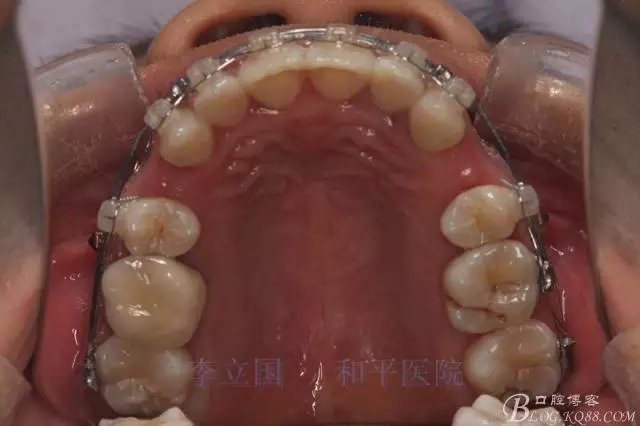

1.拔除14、24、31。

2.Damonclear排齊整平。

3.微種植支抗內(nèi)收上下前牙。

1.患者上前牙直立,面型前突,典型的嘴凸牙不吐,關(guān)鍵是前牙轉(zhuǎn)矩控制,建議使用高轉(zhuǎn)矩托槽。

3.上頜應(yīng)用支抗釘。表麻下在56牙槽間隔植入,注意因使用的為鈦合金釘,一直保持植入角度與骨面成60度角,不要垂直植入再改變角度。要求即刻加載,即刻加載力值2盎司。

4.使用長(zhǎng)牽引鉤,使?fàn)恳咏项M骨阻抗中心,防止上頜骨的順時(shí)針旋轉(zhuǎn)。

5.回收過(guò)程中,上下前牙輕搖椅,防止覆合加深。